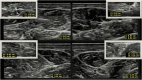

Findings: We describe a case of a 68-year-old woman with slowly progressive ataxia with paresthesia. Laboratory tests were normal. Total spine MRI showed a C4 posterior spinal cord lesion. Lumbar puncture was positive for oligoclonal bands with normal IgG index and protein level. Paraneoplastic antibodies were not detected. Electromyography showed nonlength dependent sensory neuropathy. The patient was treated with intravenous immunoglobulin for suspected dysimmune myelitis. Over 6 years, she progressively developed other neurological manifestations evoking CANVAS. Nerve conduction study showed isolated sensory impairment over the years and peripheral nerve ultrasound revealed abnormally small nerves. Further genetic testing confirmed the diagnosis.